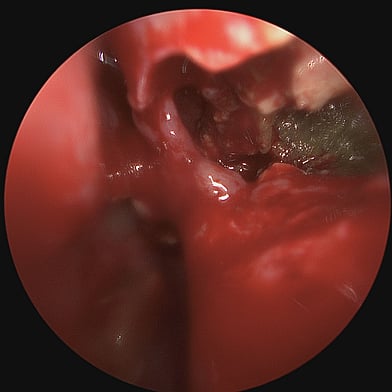

Diagnosing chronic rhinosinusitis involves a comprehensive evaluation, which may include medical history and physical examination, nasal endoscopy, imaging studies, allergy testing, and conducting nasal and sinus cultures.

Treatment can be initiated with regular medications like nasal steroid sprays, anti-histamine tablet and sprays, antibiotics, nasal saline sprays, or oral corticosteroids. But specific problems causing rhinosinusitis may be treated with Functional Endoscopic Sinus Surgery (FESS).